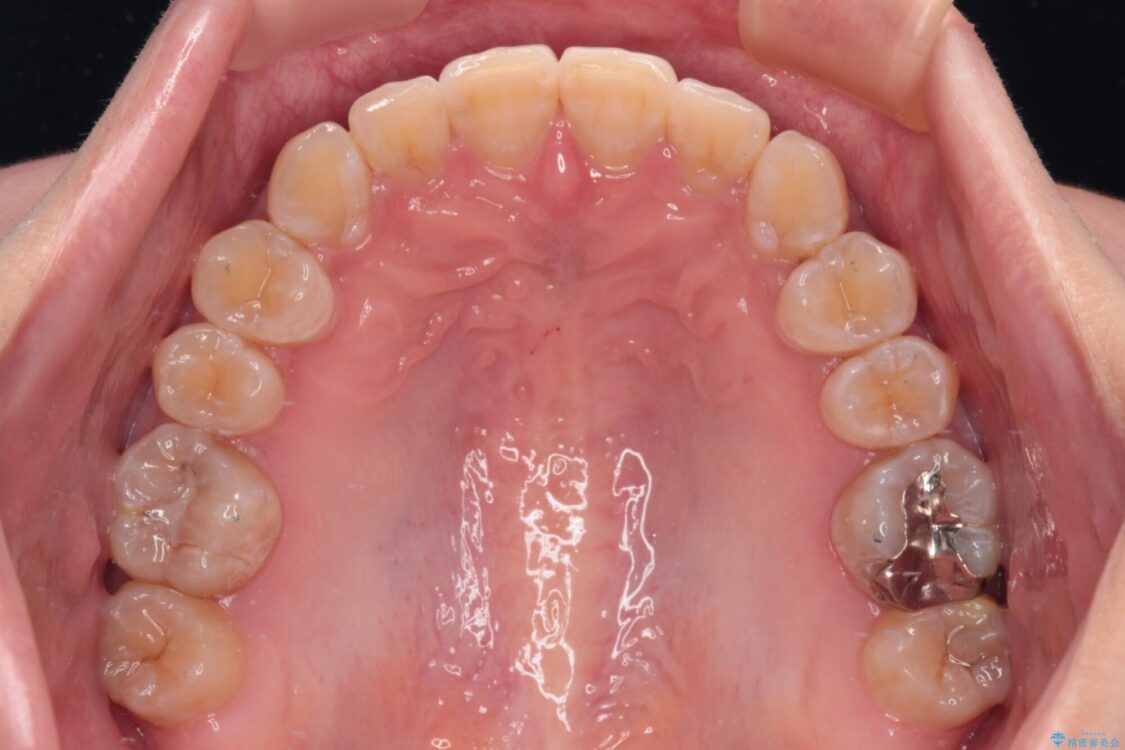

下顎の八重歯を気にして来院された患者様です。

下顎前歯にデコボコが集中していたため、顎間ゴムによる後方移動とIPR(歯と歯の間を削ること)により歯列を整えることとしました。

治療前、下顎前歯のデコボコが集中しており、奥歯の咬み合わせは、上顎に対して下顎が前方位にある状態でした。下顎の歯列を後方へ移動させる治療はインビザラインの得意とするところですので、1年程度で無事に治療を終えることができました。

治療前

• 【モニター】下顎前歯のデコボコをインビザラインできれいに 治療前画像